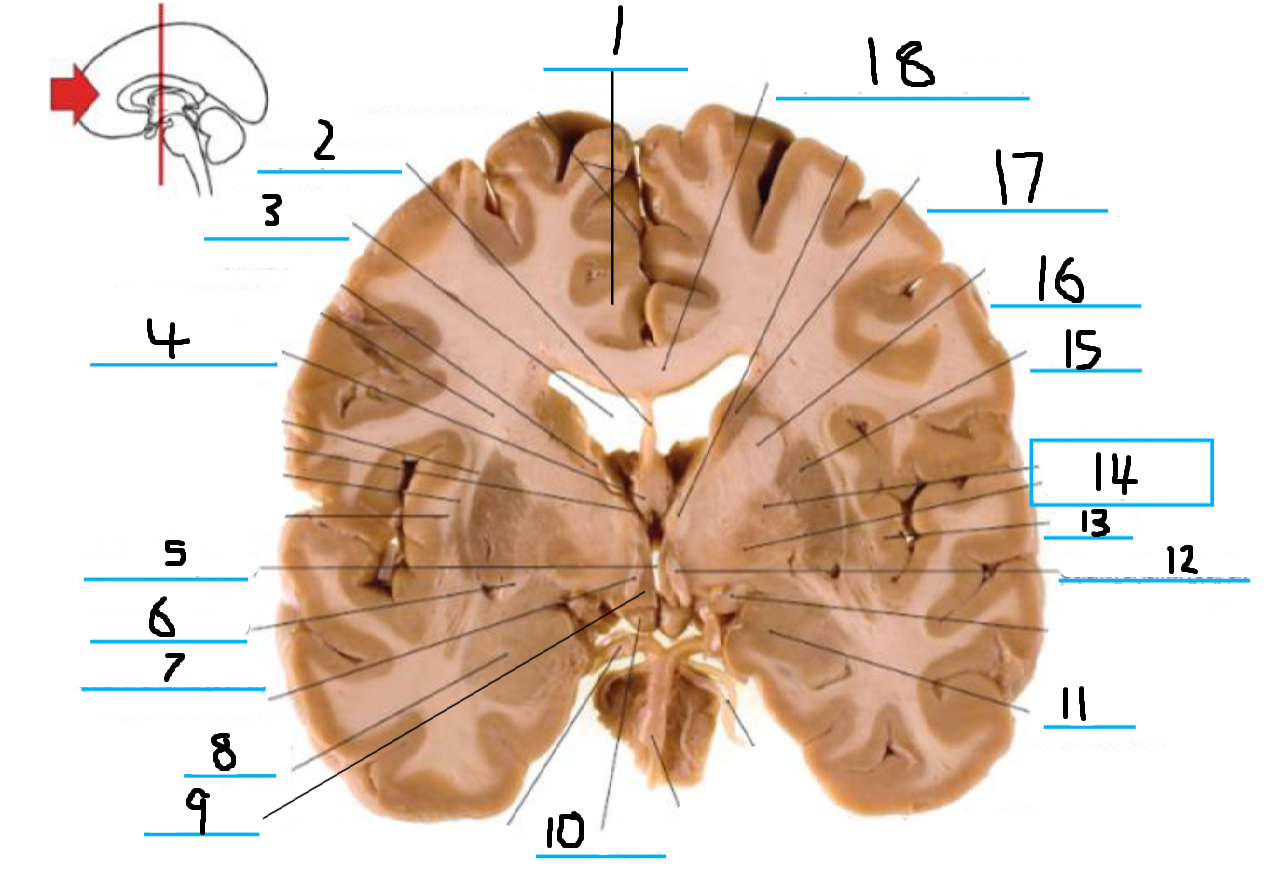

#1 is the:

Corpus Callosum

#2 is the:

Lateral Ventricle

#3 is the:

Septum Pellucidum

#4 is the:

#5 is the:

Insula

#6 is the:

Cingulate Gyrus

#7 is the:

Caudate

#8 is the:

Internal Capsule

#9 is the:

Putamen